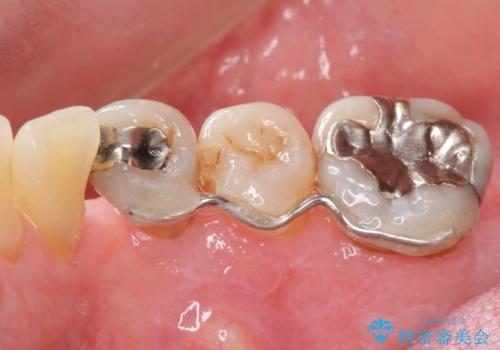

- 全顎的な重度歯周病の患者様です。

骨吸収の進行している右下臼歯部に、再生療法(骨を増やす手術))を行いました。